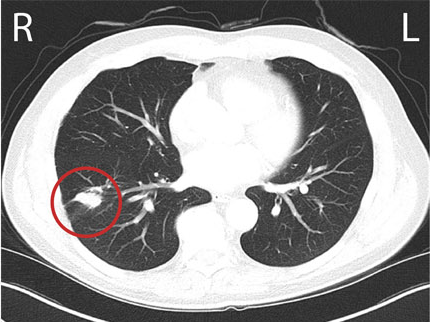

Paul's CT scan detected a 2.5 cm nodule in the lower lobe of his right lung.

A chest CT scan is similar to but much more detailed than a chest X-ray image. It allows doctors to have an accurate image of your lungs, heart, esophagus and lymph nodes.

CT stands for Computed Tomography. This painless imaging test takes many detailed X-ray images, called slices, of your lungs and the inside of your chest. Computer software combines these slices to create three-dimensional (3D) models to help show the size, shape, and position of your lungs and structures in your chest.

- The location and size of any tumour in the lung